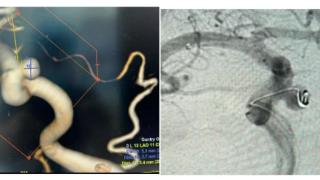

微创手术化解“脑内炸弹”,济南南郊医院脑科精准治愈颈内动脉瘤..[详情]

全国首例!郑州市第七人民医院团队让患者重获“心”生..[详情]